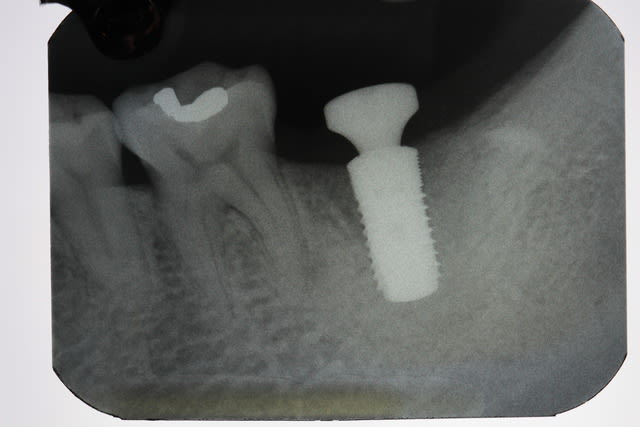

Img 2206 tbw3xx - Eugenol